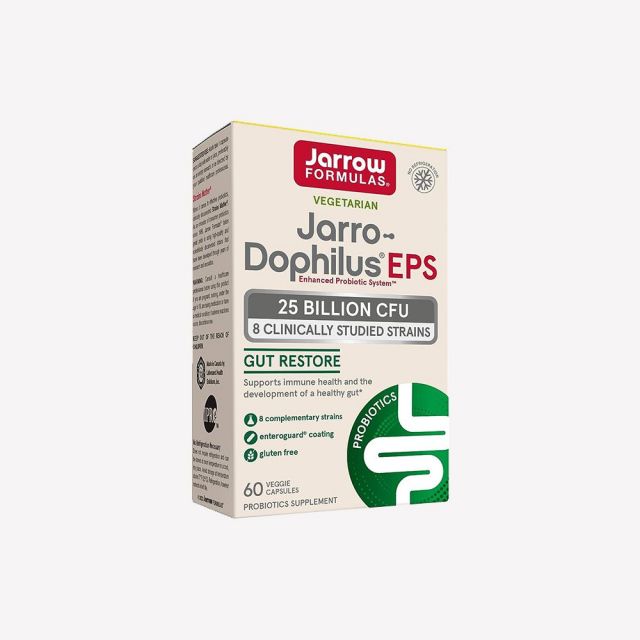

3자로 도필러스 유산균의 특징은 무엇인가요?자로 포뮬러의 도필러스는 EnteroGuard®라는 특허 코팅기술을 이용하여 유산균들의 안정성을 확보했습니다. 특히 실온에서 보관할 수 있게 되었으며 이동 중에도 간편히 섭취할 수 있습니다. 또한 장에서 용해되도록 코팅해 유산균들이 혹독한 위산환경에도 무사히 살아남아 장까지 도달할 수 있게 되었습니다. 또한 최소 250억 마리의 살아있는 유산균을 보장합니다.

4어떤 유산균들이 들어있나요?자로 도필러스는 4개의 속(屬)으로 구성된 무려 8가지의 다양한 복합균주가 들어있습니다. Lactobacillus, ifidobacterium, Lactococcus, Pediococcus, 의 4개의 속에, Lactobacillus rhamnosus R0011, Lactobacillus helveticus R0052, Pediococcus acidilactici R1001, Lactobacillus casei R0215, Bifidobacterium longum BB536, Lactobacillus plantarum R1012, Bifidobacterium breve R0070, Lactococcus lactis ssp. lactis R1058 등 여덟가지의 복합균주가 들어있습니다. 유산균은 종에 따라 기능하는 것이 다르고 각 균주마다 성장 속도가 다릅니다. 예로, 성장 속도가 느린 균주의 경우, 오랜 시간 이동해야 장까지 도착할 수 있다는 것을 의미하니, 양이 많아야 유리합니다. 따라서, 단일 유산균 제품보다 여러 균이 골고루 섞인 복합 유산균 제품이 좀 더 좋은 효과를 볼 수 있습니다.

5품질은 어떤가요?자로 포뮬러는 2019년 컨슈머랩 (ConsumerLab)에서유산균 제품군에 대해 소비자만족도 1위를 차지한 1등 유산균 브랜드랍니다. 컨슈머랩 (ConsumerLab)은 건강기능식품에 관련된 퀄리티에 대해 아주 혹독한 테스트를 하는 제3의 독립 미국평가기관입니다. 소비자들이 이곳에서 정보를 얻기 위해서는 일정 회비를 내야하며 제조업체가 CL 인증을 받기 위해서는 시장에서 랜덤으로 구입한 해당제품을 샘플로 삼아 위의 기준에 부합되는지 12개월간 매달마다 시행되는 테스트를 거쳐야 합니다. 이렇게 엄격한 독립기관에서 매년마다 실시하는 중요한 설문조사가 있으니 바로 수천 명의 소비자를 대상으로 한 소비자만족도입니다.